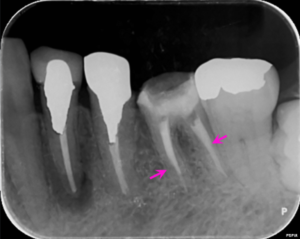

左下6番の歯の根の中を清掃し終わった後に内部に薬を詰めた直後のレントゲン写真です。

薬は根の中に緊密に詰まっています(矢印ピンク)。